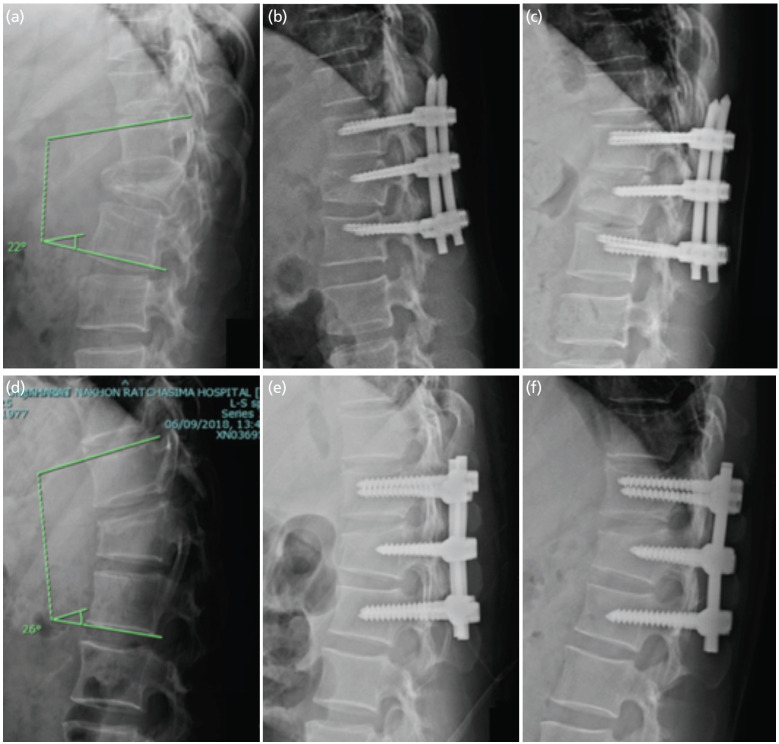

Results: Between January 2018 and October 2019, 31 patients received PPSF and 30 OPSF. Mean intra-operative blood loss was 66.45 (±44.29) ml for PPSF vs 184.83 (±128.36) ml for OPSF (p<0.001). Fluoroscopy time averaged 2.36 (±0.76) minutes for PPSF vs 0.58 (±0.51) minutes for OPSF (p<0.001). No significant differences existed in operative time or post-operative VAS scores. Radiographic parameters (kyphosis angle and vertebral height ratios) didn't significantly differ post-operatively or at 12 months. However, ODI scores differed significantly at 6 months (p=0.025), with no difference at 12 months.

Conclusion: In this trial, PPSF was comparable to OPSF in improving ODI scores at 12 months but showed earlier improvement at 6 months and reduced blood loss. Radiographic outcomes remained similar between groups over 12 months.